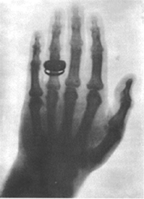

If you have ever broken a bone you have had an x-ray done to see what the break looks like. Can you make out the image to the left? It is a left hand with a ring on the finger. An X-ray camera works like any other camera except it gives off invisible energy rays called X-rays. These X-rays travel through your skin. An X-ray camera won't work unless it finds something hard to stop the rays. The X-rays bounce off of your bone and back to the camera. The x-ray picks up the dense parts of the bone. The denser the bone, the more rays that were bounced back, the lighter the bone appears on the "film." (The picture to the left is reversed.)